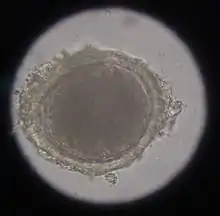

The most common roundworm in most cats is toxocara mystax (syn. toxocara cati), infestation with toxascaris leonina is less common. Only in ocelots in Texas was T. leonina detectable in every animal, making it the most common parasite,[2] and in bobcats in Nebraska it was observed almost as often as T. mystax.[3] Both species of roundworm occur worldwide and roundworm infestation is a very common endoparasitosis. The adult roundworms, up to 10 cm long, live in the small intestine. The female worms produce a large number of eggs, which are released into the environment with the feces. The infective larvae develop in the eggs after about four weeks.

In the case of worms in vomit, the diagnosis can already be made without special examinations. A roundworm infestation can be detected with relative certainty by microscopic detection of the eggs extracted from the feces using the flotation method.

Infection with hookworms often remains asymptomatic in cats. In more severe infestations, they can cause emaciation, anemia or diarrhea. As with roundworms, the infection is detected by detecting the eggs in the feces using a flotation method. They are oval, smaller than roundworm eggs (about 60×40 µm in size) and furrowed stages are already visible inside when the eggs are laid.

In the same animal, usually only two to ten cat tapeworms are found, and they excrete about four to five limbs daily. These elongated trapezoidal structures may already be visible to the naked eye in the anal region. The coated oncospheres, which are about 35 µm in size, can be detected in the feces using flotation methods. In one study, an infestation rate of 25.9% was determined in autopsies, of which only 10% were detected by flotation and 27% by centrifugation.[10] In addition, the eggs cannot be distinguished morphologically from those of other members of the taeniidae (including the fox tapeworm).